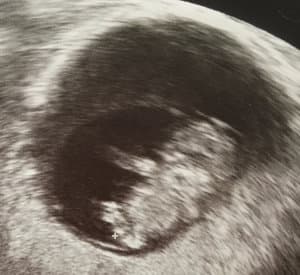

In der 10. Woche war dann auch schon unser zweiter Termin beim Frauenarzt und dort durften wir im Ultraschall noch einmal das Herzchen schlagen sehen und die Ärztin sagte uns, dass das Baby mittlerweile 2,5 cm groß ist, was super für die errechnete Woche sei. Zudem sieht man mittlerweile, dass das wirklich mal ein Mensch wird, was wir beide ziemlich beeindruckend fanden. Auch habe ich bei diesem Termin meinen Mutterpass bekommen, auf den ich ganz stolz bin :) . Als Geburtstermin wurde (wie ich selber schon ausgerechnet hatte) der 27.11 angegeben, der Countdown hat nun also wirklich begonnen.